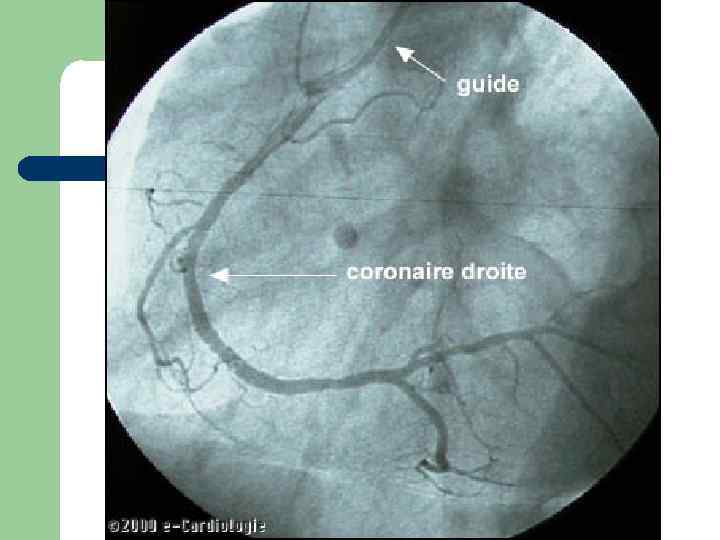

Коронароангиография «золотой стандарт» диагностики стенозирующих поражений коронарных артерий и ключевой метод для принятия решения о необходимости и способе реваскуляризации. Но… помнить концепцию Glagov!